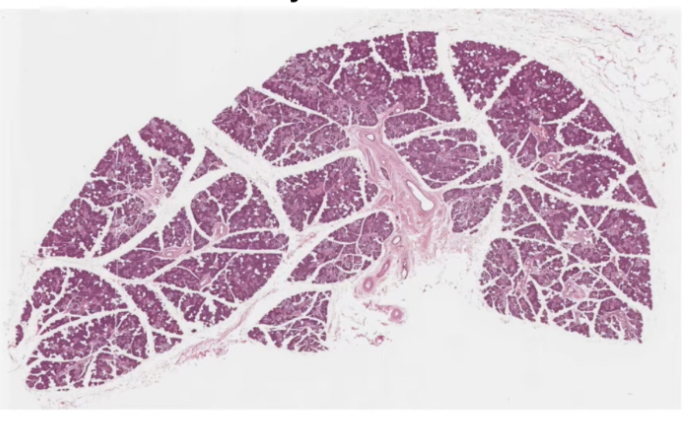

Thymus

Maturation and proliferation of lymphocytes

Surrounded by CT capsule

Several lobes separated by CT septa

Each lobe has dense cortex and inner paler medulla

Hassalls or thymic corpuscles

Flattened epithelial reticular cells in concentric layers